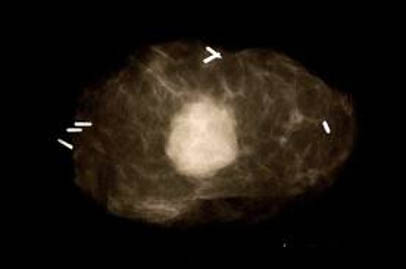

Tumours that are not easily palpable will require localisation technique prior to the surgery. Most commonly, a fine wire with a small hook on the end is inserted into the middle of the tumour under either ultrasound or mammogram guidance, just prior to the procedure.

This is called HOOKWIRE LOCALISATION.

Other localisation techniques use carbon or radioisotope localisation. The use of intraoperative ultrasound is now becoming an evolving technique to find an impalpable tumour with precision and very little destruction to surrounding tissue.